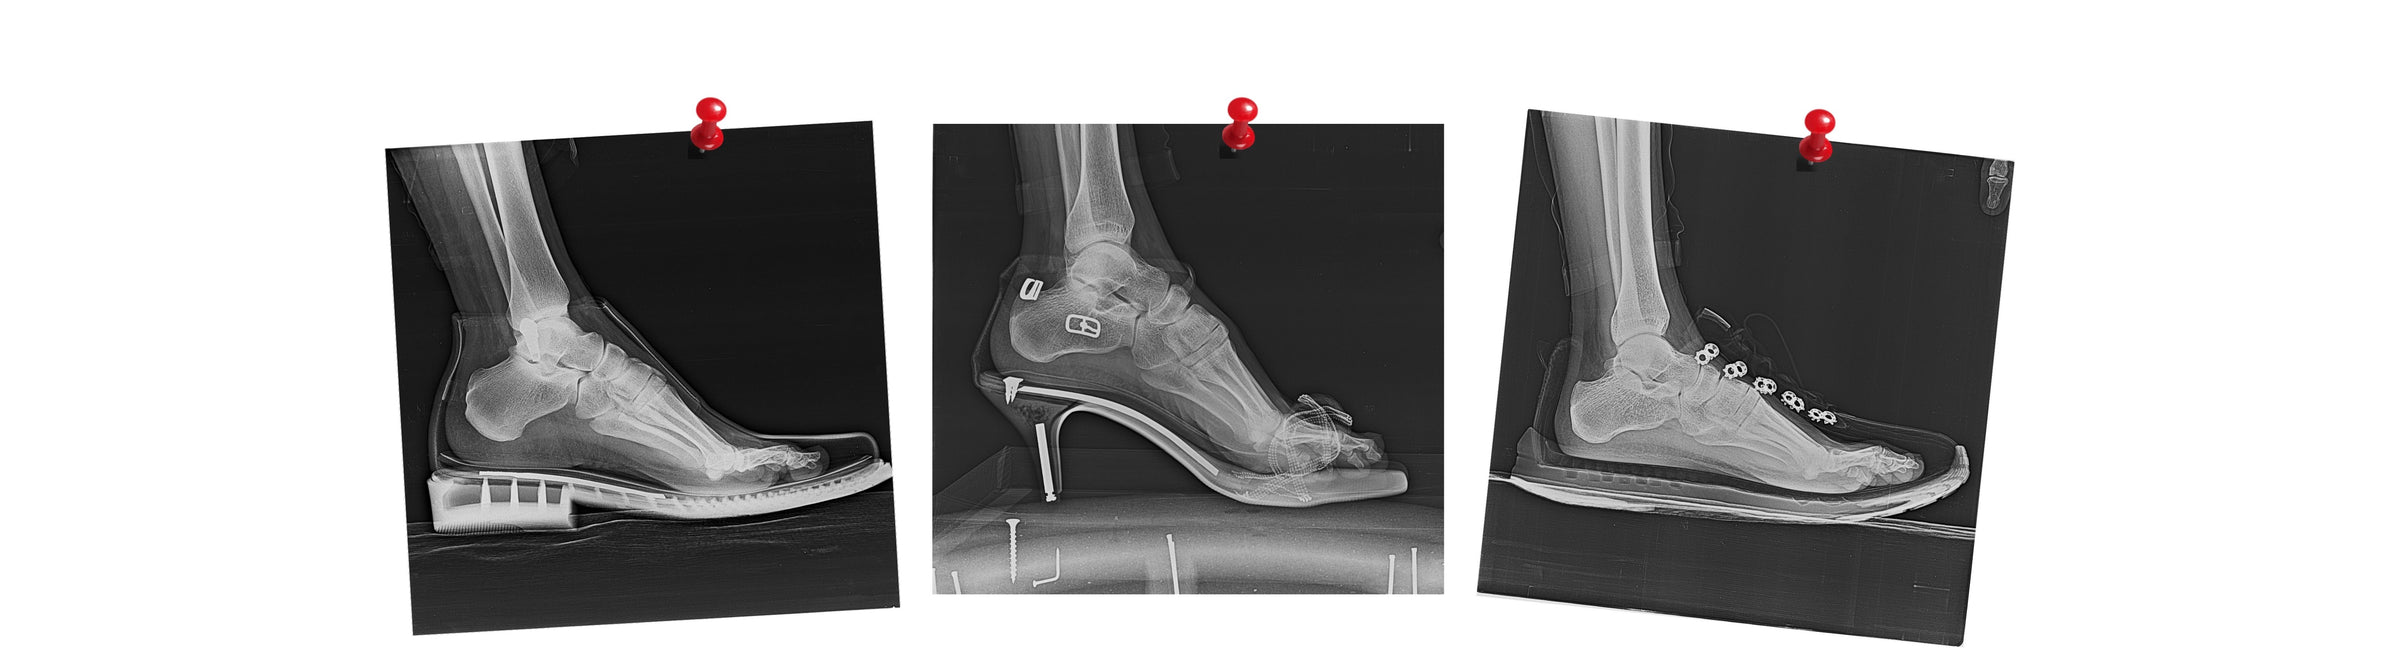

Harmful environment for your feet

Regular shoes with a narrow toe box, heel elevation, and thick, stiff soles create an artificial environment for your feet.

They restrict the natural movement of your feet and reduce sensory feedback from the ground. This artificial environment negatively impacts your entire body

Heel Elevation vs. Zero-Drop Sole

Understanding the Impact Zero-Drop Design on Foot Health

Zero-Drop Sole

A flat sole without a heel promotes a natural walking posture and stance. It helps to distribute weight evenly across the entire sole of the foot.

This reduces strain on the feet, back, hips, and knees, and supports the balance of the entire body.